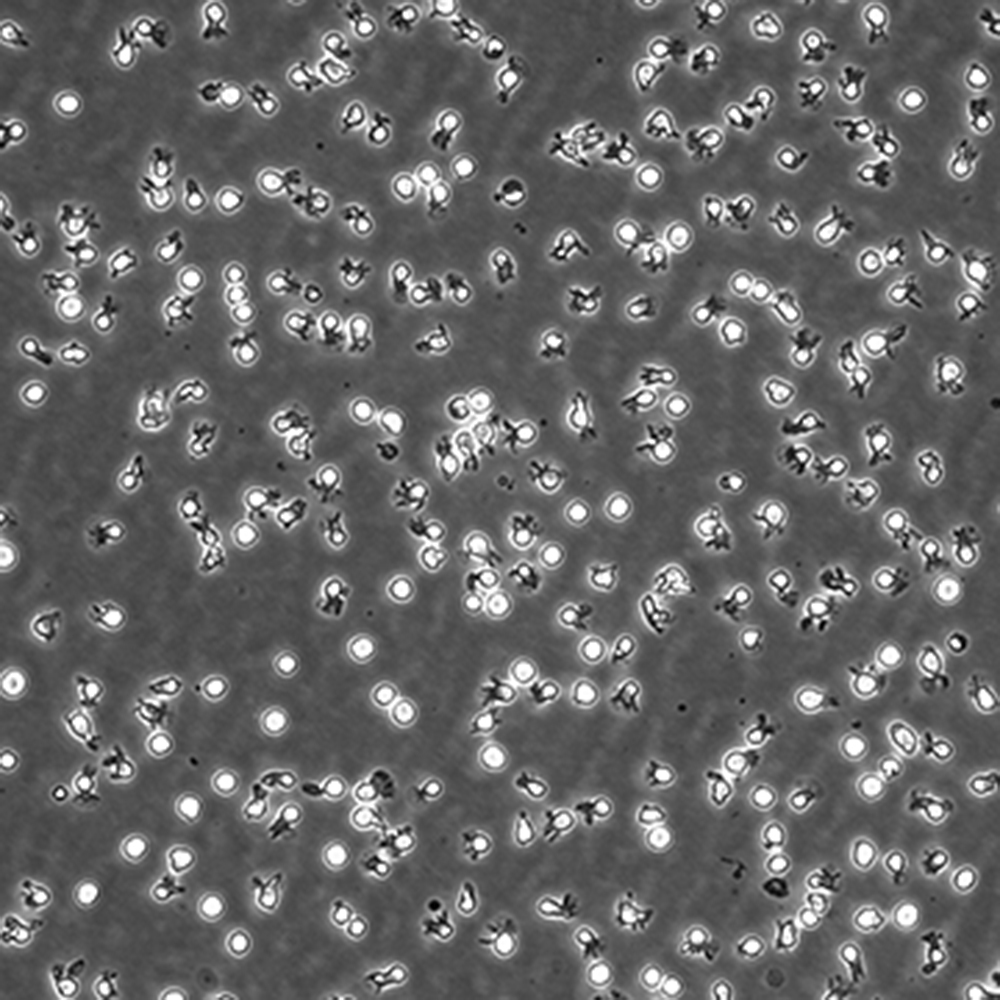

中文名稱 人彌漫大B細胞淋巴瘤細胞

組織來源 彌漫大B細胞淋巴瘤;男性

生長特性 懸浮

培養基 IMDM,90%;FBS,10%;雙抗。

傳代方法 Maintain cultures at a cell concentraion between between 1 X 10(5) and 1 X 10(6) viable cells/ml.

培養條件 Atmosphere: Air, 95%; CO2, 5%。Temperature: 37℃